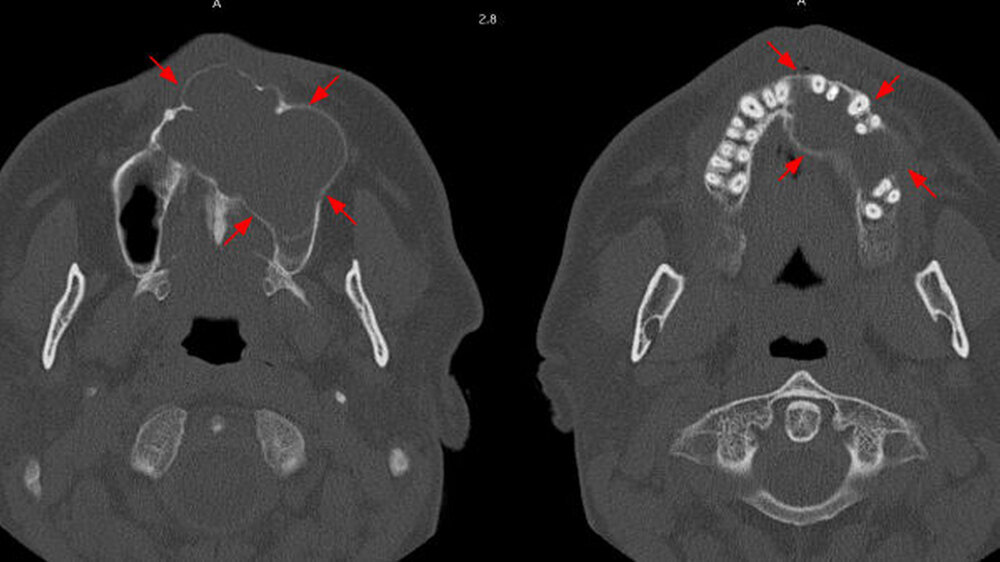

Auf den axialen Schnitten der Computertomografie ist sowohl die palatinale Ausdehnung wie auch die Einbeziehung der Oberkieferzähne im zweiten und teilweise ersten Quadranten gut zu erkennen (Abbildung 5c). Insgesamt stellt die diagnostische Bildgebung dar, dass es sich um einen verdrängenden, nicht destruierend-infiltrierenden Prozess handelt, der mit sehr hoher Wahrscheinlichkeit von der bereits vor sechs Jahren diagnostizierten Raumforderung in Regio 24 und 25 ausging. Als Verdachtsdiagnose konnte somit von einer Raumforderung zystischen Ursprungs ausgegangen werden.